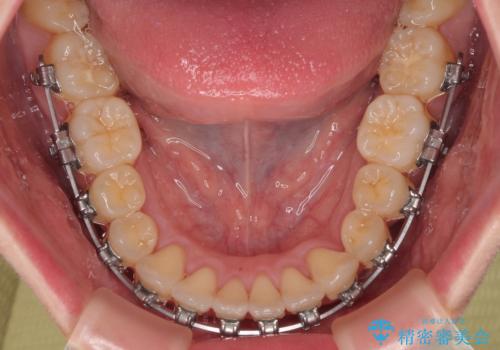

- メタルブラケット

上顎の急速拡大装置を使用して上顎骨を側方に拡大することで上顎歯列を拡大し、下顎歯列も拡大できるようにすることで、歯列を整えることとしました。

歯列矯正では基本的に骨格を改善することはできませんが、急速拡大装置(MARPE)を使用することで上顎骨を側方に拡大させることができ、咬合状態を大きく改善することができます。